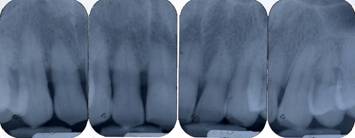

Pre-operative periapical radiography with a Rinn Centering was performed [fig. 1].

Fig 1

Pre-operative periapical radiography

The examination technique was standardized to obtain radiographs as similar as possible. Impressions were made at the first examination and saved for follow-up control examinations. Radiographs were performed immediately before treatment and at 10 days, and 6, 9, and 24 months after treatment.